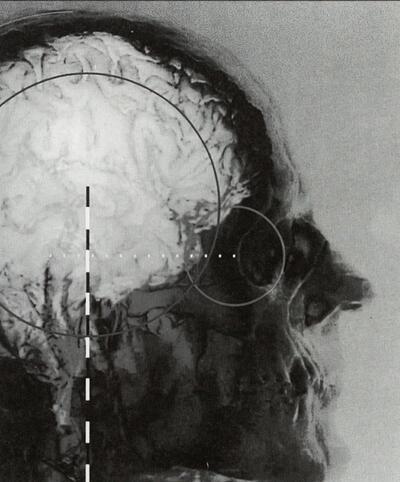

Het brein